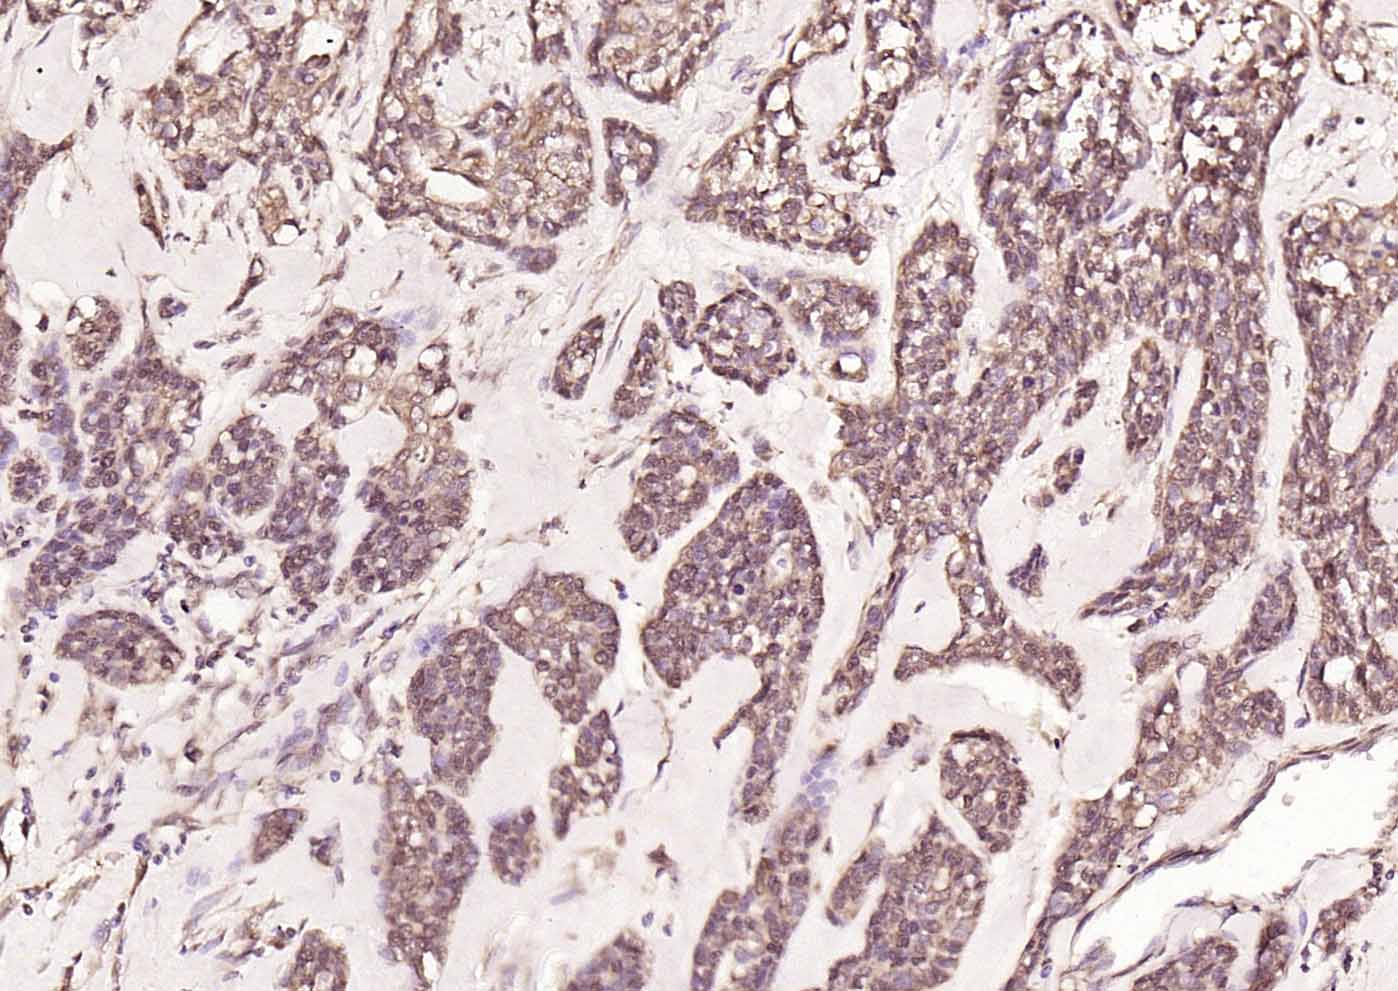

| 英文名称 | HDAC2 Rabbit pAb |

| 中文名称 | 组蛋白去乙酰化酶2抗体 |

| 产品应用 | IHC-P=1:100-500, IHC-F=1:100-500, IF=1:100-500 Not yet tested in other applications. |

| {IHC-P} | {1:100-500} |